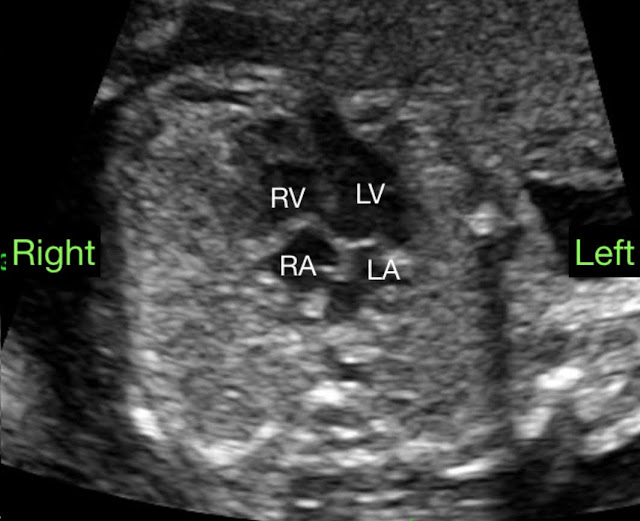

孕婦A在妊娠22週時來台兒做中期胎兒結構檢查,發現胎兒心臟軸向較偏中線(圖一),且左心室有一憩室突出至胸壁之外(圖二),憩室的尖端與臍帶緊靠在一起,但兩者血流並無相通。詳細檢查心臟其他結構,除了一常見的變異:持續性左上腔靜脈(persistent left superior vena cava)之外,並無其他異常發現。根據上述超音波影像,我們的胎兒診斷為Pentalogy of Cantrell。妊娠27週時,核磁共振影像顯示左心室憩室突出胸壁之外,且前胸壁有大約2公分長的軟組織缺損,除此之外,並未發現橫隔膜缺損或腹壁缺損(圖三)。 妊娠33週追蹤時,以冠狀切面觀察胎兒胸骨發育,僅見三個骨化中心; 對照正常胎兒,於28週時已可觀察到4個骨化中心(圖四),因此推測胎兒下段胸骨發育異常。

圖一:胎兒心軸較偏向中線(mesocardia)。(台兒診所臨床個案)